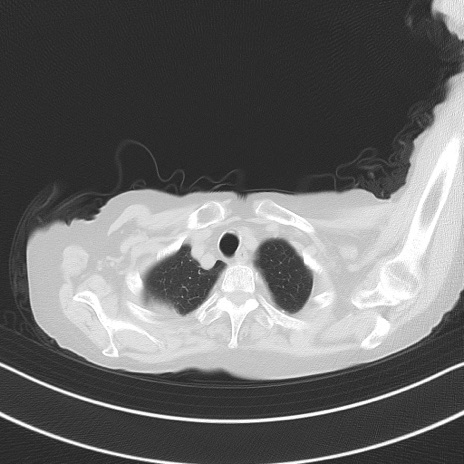

症例40(横断像)他院1日前

横断像

他院CT